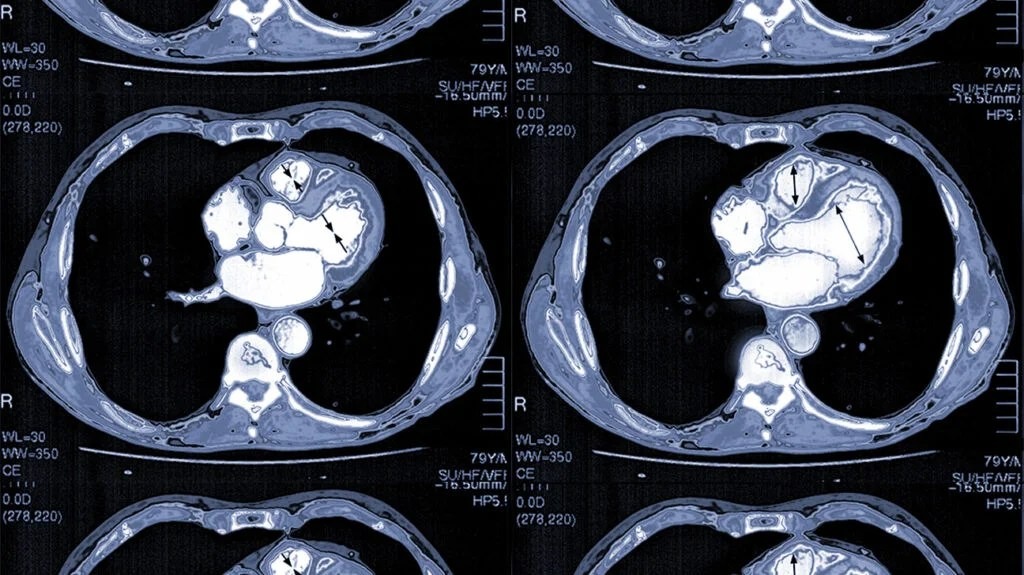

Coronary angiography is an advanced imaging technique that offers a detailed look at the heart’s blood vessels. This minimally invasive test uses a special dye visible on X-rays, combined with a catheter inserted into the coronary arteries. While more invasive than other diagnostic methods, coronary angiography is indispensable in evaluating coronary artery disease and planning interventions. Some key uses of coronary angiographies include: